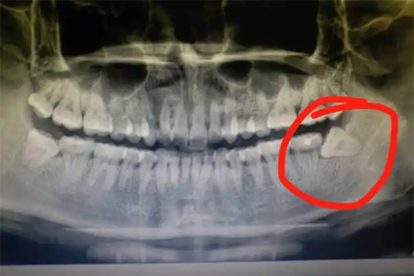

近中阻生的智齿常顶撞第二磨牙远中面,导致邻牙牙根吸收或龋坏。早期可见第二磨牙远中邻面发黑、冷热敏感,后期可能出现自发痛或咬合痛。通过口腔全景片可明确诊断,邻牙已受损时需同时处理智齿和第二磨牙,必要时进行根管治疗或全冠修复。

埋伏阻生的智齿可能刺激颌骨形成含牙囊肿,初期无明显症状,随囊肿增大可出现骨膨隆、牙齿移位。X线片显示圆形透射影伴阻生牙牙冠。需手术摘除囊肿并拔除智齿,较大囊肿可能需植骨修复骨缺损。